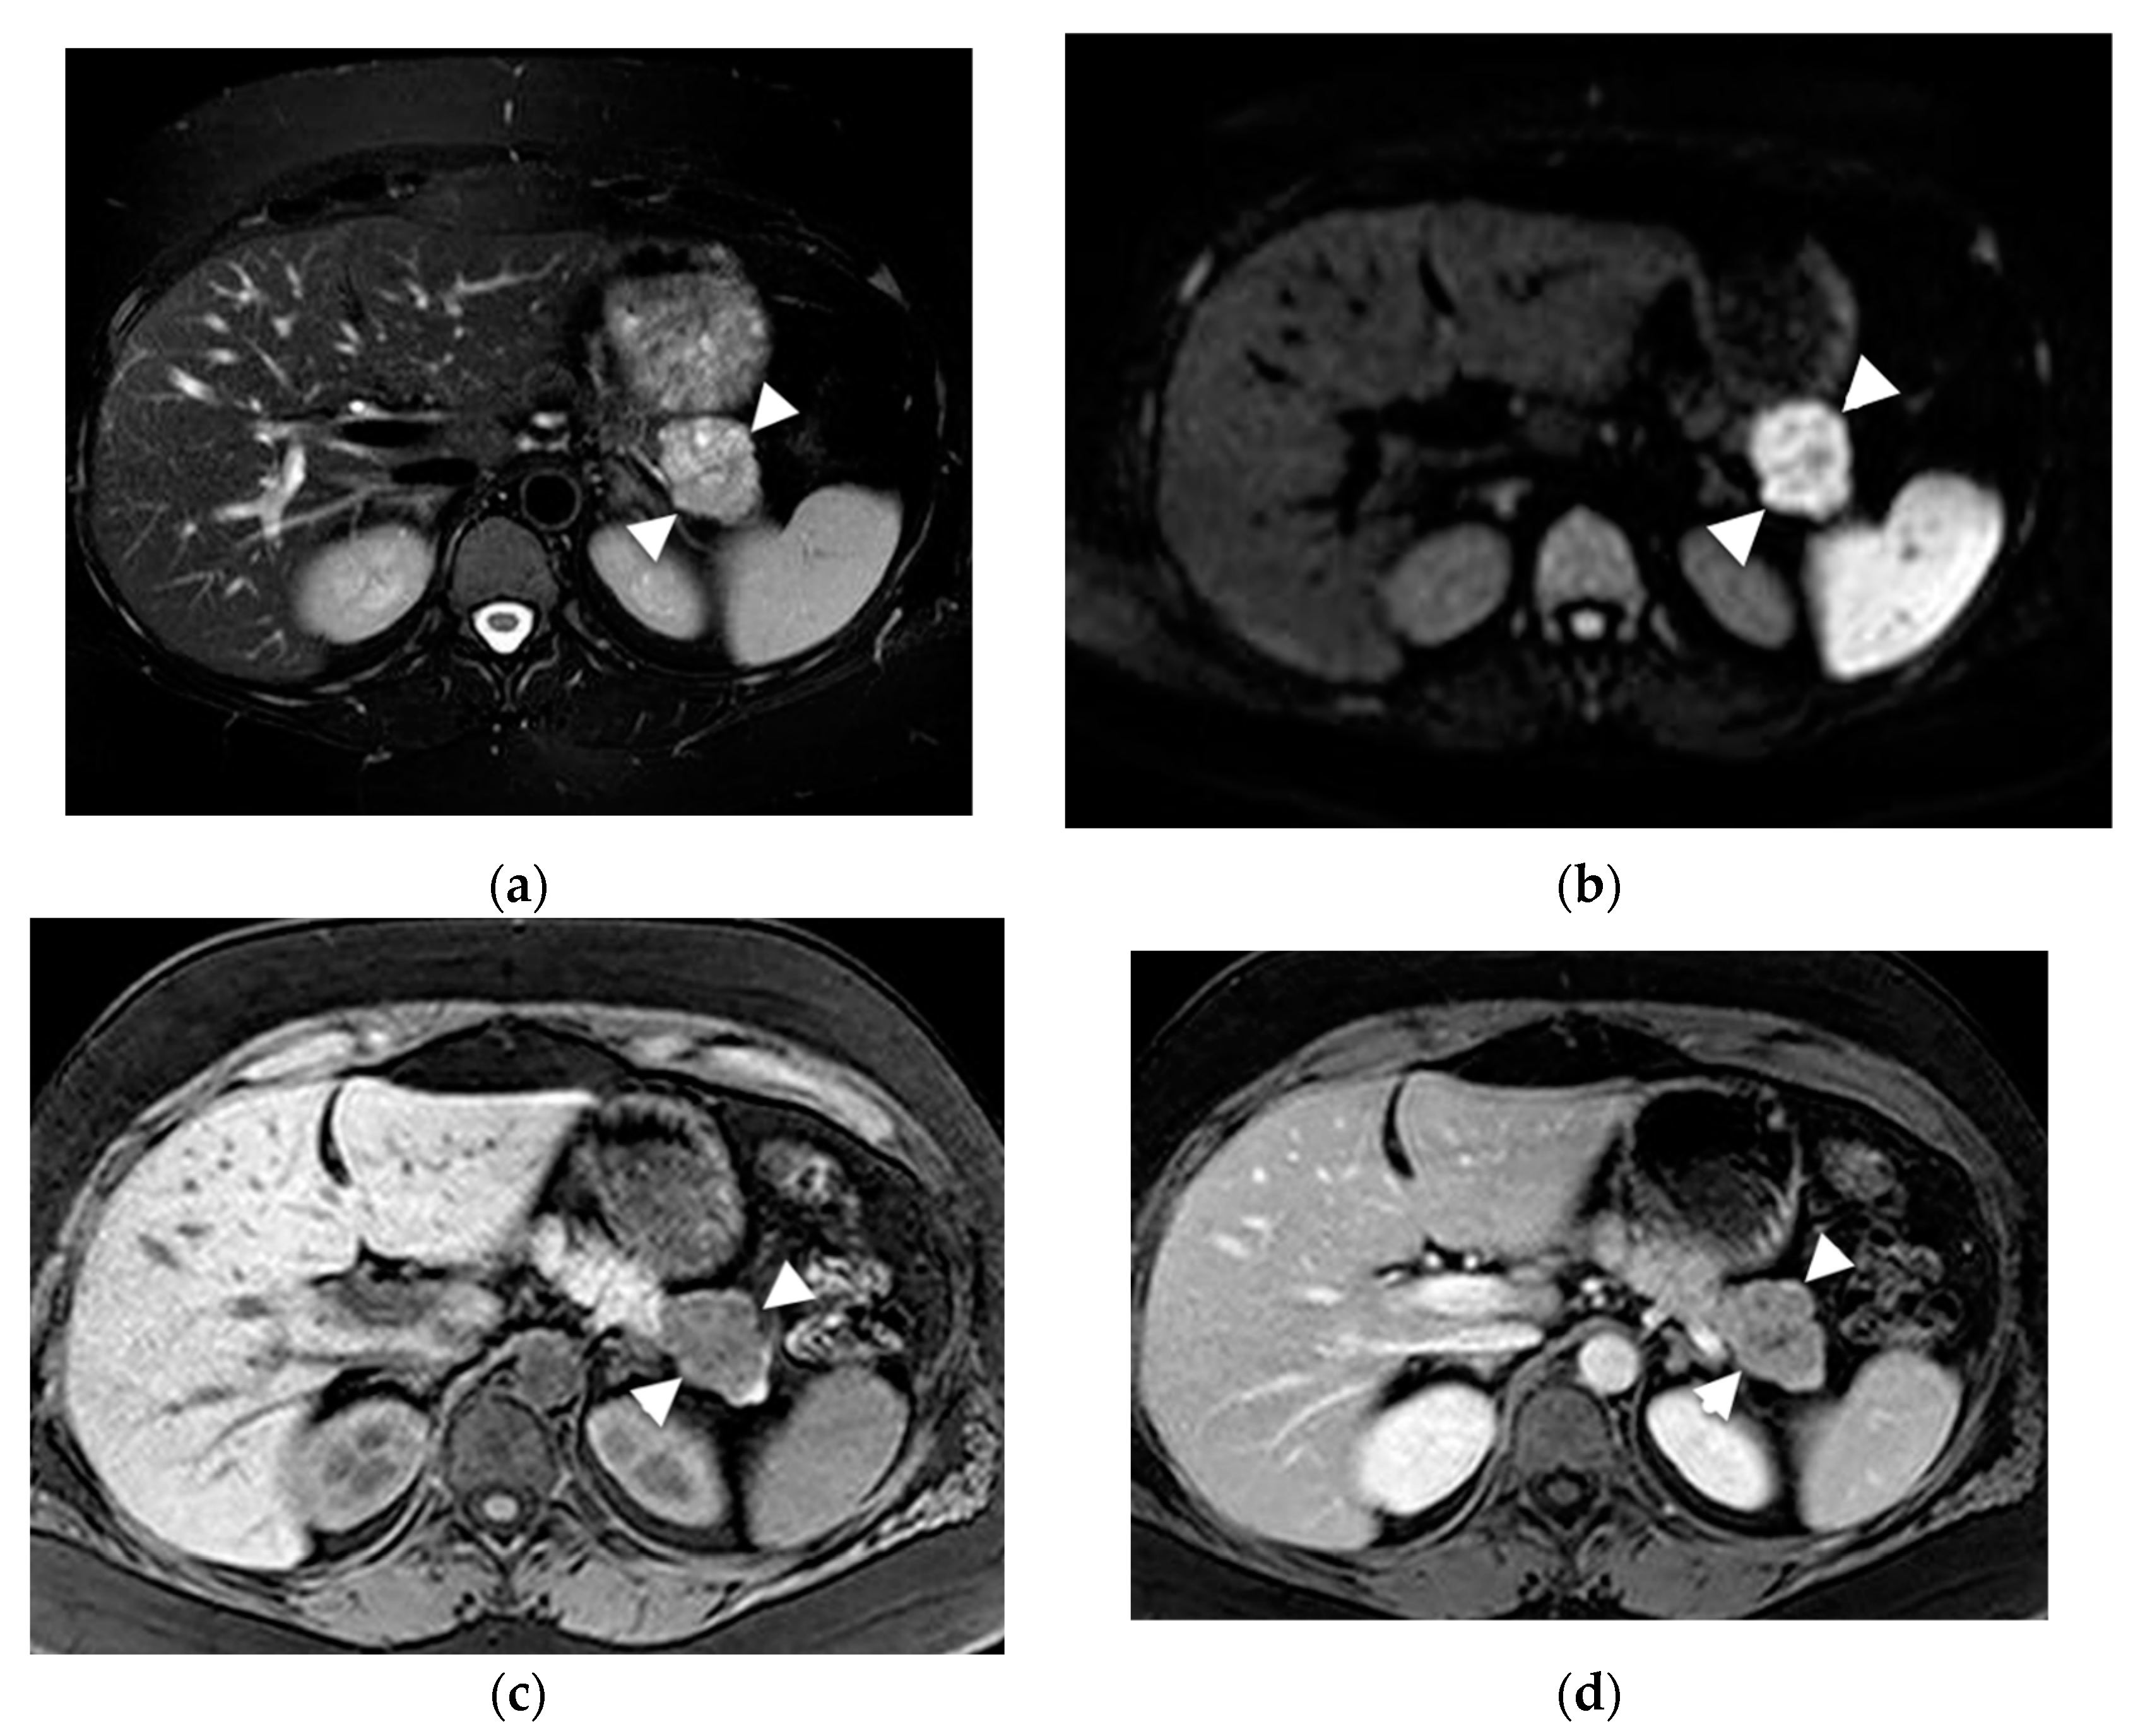

- Mamone, G.; Barresi, L.; Tropea, A.; Di Piazza, A.; Miraglia, R. MRI of mucinous pancreatic cystic lesions: A new updated morphological approach for the differential diagnosis. Updates Surg. 2020, 72, 617–637. [Google Scholar] [CrossRef] [PubMed]

- Garces-Descovich, A.; Beker, K.; Castillo-Angeles, M.; Brook, A.; Resnick, E.; Shinagare, S.; Najarian, R.M.; Mortele, K.J. Mucinous cystic neoplasms of the pancreas: High-resolution cross-sectional imaging features with clinico-pathologic correlation. Abdom. Radiol. 2018, 43, 1413–1422. [Google Scholar] [CrossRef]